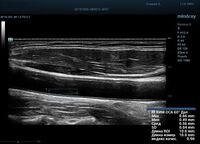

Функция в ультразвуковых аппаратах

На сегодняшний день измерение IMT происходит автоматическим путем при использовании функции AUTO-IMT. Необходимо указать прибору зону интереса, стандартной длиной (1 см), в которой происходит отслеживание кромок и выдача максимального, среднего и минимального значения. УЗИ аппараты компании Mindray среднего, экспертного и премиального класса снабжены данной функцией и позволяют контролировать не только полученные значения, но и оценить точность измерения кромки в конкретной зоне по индексу качества. Используя индекс качества, легко решить, можно ли использовать полученное значение.

Форма отчета стала удобной: в единой таблице сводятся измерения левых и правых артерий, указываются все значения с автоматическим расчетом общего среднего показателя. Если один из показателей измерения резко выбивается и считается недостоверным – его можно исключить из расчета.

Для более искушенных в результате исследования существует качественно новый уровень измерения комплекса интима-медиа. Система RIMT использует нативные акустические данные (RF-Data) и проводит несколько измерений в режиме реального времени, получая измерения IMT с точностью до 5 мкм. Измерения проводятся в течении шести сердечных циклов, таким образом резко снижается вероятность погрешности.